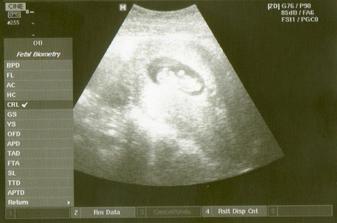

26.9...........UTZmiminko kope nožičkama a mává ručičkama---nádhera.Je trošku starší..12+1